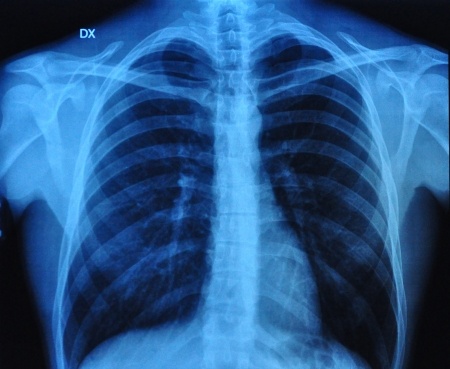

Obturacyjny bezdech senny stanowi niezależny czynnik ryzyka wystąpienia zatorowości płucnej. Do rozpoznawania nawrotu zatorowości płucnej wykorzystywana jest - między innymi - ocena stężenia D-dimerów w surowicy. Angela García Suquia i wsp. zaprojektowali badanie mające na celu ocenę z jaką częstością obserwuje się podwyższone wartości D-dimerów (>500 ng•mL−1) po zakończeniu leczenia przeciwkrzepliwego z powodu zatorowości płucnej wśród pacjentów z rozpoznanym obturacyjnym bezdechem sennym oraz u osób wolnych od tego schorzenia. Wyniki badania opublikowano na łamach czasopisma European Respiratory Journal.

Obturacyjny bezdech sennych rozpoznano u 64 (74.4%) pacjentów z grupy badanej (u których wystąpiła zatorowość płucna) oraz u 41 (46.11%) osób z grupy kontrolnej (u których nie wystąpiła zatorowość płucna). Przeprowadzona analiza statystyczna wykazała istotnie wyższe stężenia

D-dimerów wśród pacjentów z zatorowością płucną oraz obturacyjnym bezdechem sennym, w porównaniu z osobami, u których OBS nie występował. Stężenia D-dimerów korelowały dodatnio z wskaźnikiem AHI oraz nocną hipoksemią.

Stwierdzono również, iż wśród osób po zatorowości płucnej z towarzyszącym obturacyjnym bezdechem sennym istotnie częściej utrzymywały się podwyższone wartości D-dimerów w surowicy po zakończeniu leczenia przeciwkrzepliwego w porównaniu z osobami, które na OBS nie chorowały (35.4% vs 19.0%, p=0.003).

Reasumując, autorzy badania potwierdzili, iż u osób po przebytej zatorowości płucnej z towarzyszącym obturacyjnym bezdechem sennym istotnie częściej utrzymują się podwyższone stężenia D-dimerów w surowicy po zaprzestaniu leczenia przeciwkrzepliwego, w porównaniu z osobami, które na OBS nie chorują.